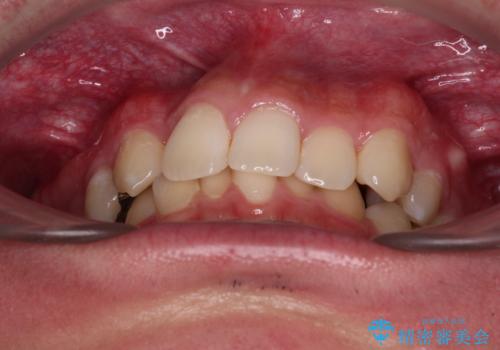

- 今回ご紹介するのは、

「全体的なデコボコ(叢生)」「上下の正中のずれ」 を主訴として来院された20代男性の患者様の症例です。

叢生が強く、歯が並ぶスペースが不足していたため、

上下左右の第一小臼歯を抜歯して、矯正治療のための適切なスペースを確保する計画としました。